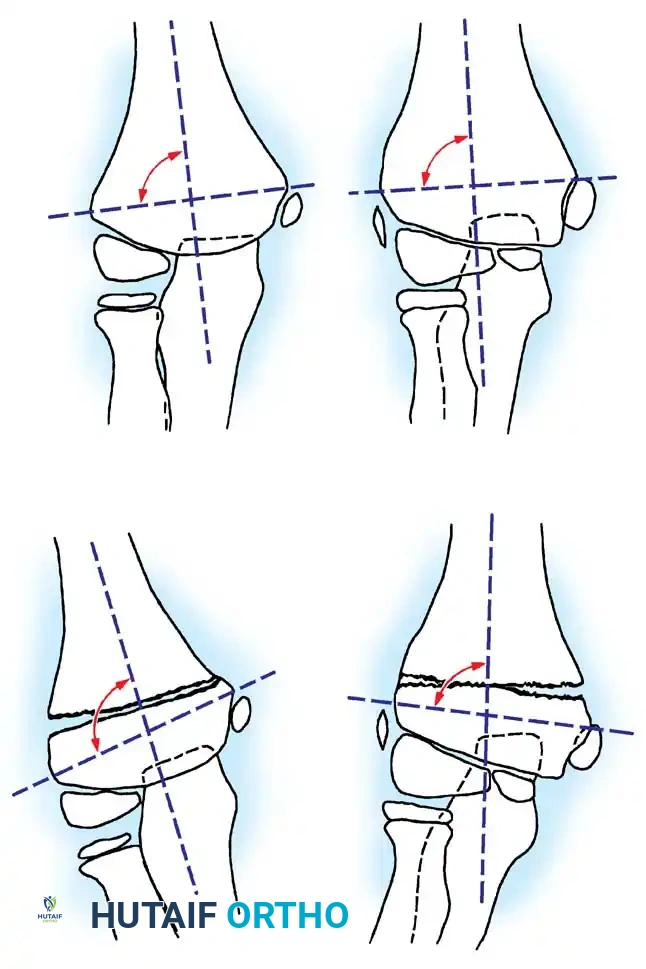

Classifications of Radial Neck Fractures

Historically, numerous classifications have been proposed, including those by Vostal, Newman, O’Brien, and Jeffery. In contemporary practice, the Wilkins Classification—which elegantly combines the morphological descriptions of Jeffery and Newman—is the gold standard for guiding surgical decision-making.

Fig. 33-38 Wilkins classification of radial neck fractures. A, Salter-Harris type II fracture. B, Salter-Harris type IV fracture. C, Salter-Harris type I fracture.

The Wilkins Classification System:

* Type A: Salter-Harris type I and II injuries of the proximal radial epiphyses.

* Type B: Salter-Harris type IV injuries of the proximal radial epiphyses.

* Type C: Fractures involving exclusively the proximal radial metaphysis.

* Type D: Fractures occurring iatrogenically when a dislocated elbow is being reduced.

* Type E: Fractures occurring simultaneously in conjunction with an elbow dislocation.

Fig. 33-39 A, Fracture occurring when elbow dislocation is reduced. B, Fractures occurring at time of elbow dislocation.

Fractures can present as angulated, translocated (shifted), or totally displaced. In the context of an elbow dislocation, the proximal fragment may become loose within the joint space or trapped, acting as a mechanical block to reduction.

Fig. 33-40 Examples of angulation, translocation, and total displacement of radial neck fractures.